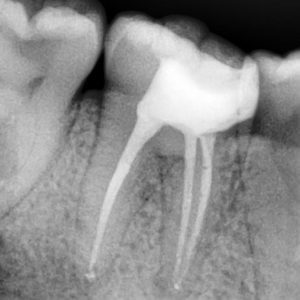

точное определение формы каналов

Высокоточный рентген показывает форму каналов и область воспаления